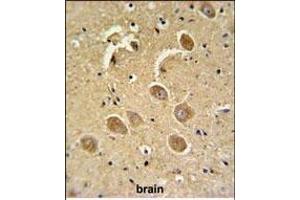

This gene encodes a protein which is a member of the cysteine-aspartic acid protease (caspase) family. Sequential activation of caspases plays a central role in the execution-phase of cell apoptosis. Caspases exist as inactive proenzymes which undergo proteolytic processing at conserved aspartic residues to produce two subunits, large and small, that dimerize to form the active enzyme. This protein cleaves and activates caspases 6, 7 and 9, and the protein itself is processed by caspases 8, 9 and 10. It is the predominant caspase involved in the cleavage of amyloid-beta 4A precursor protein, which is associated with neuronal death in Alzheimer's disease. Alternative splicing of this gene results in two transcript variants that encode the same protein. [provided by RefSeq, Jul 2008].

CASP3 适用: 人, 小鼠, 大鼠, Cow, 犬, 猴, Pig, 兔, 豚鼠, Hamster, Saccharomyces cerevisiae, 小鸡 WB, IHC, IHC (p) 宿主: 兔 Polyclonal unconjugated

Pubmed 2 references

产品编号 ABIN462092

50 μg

发货至: 中国

获取报价